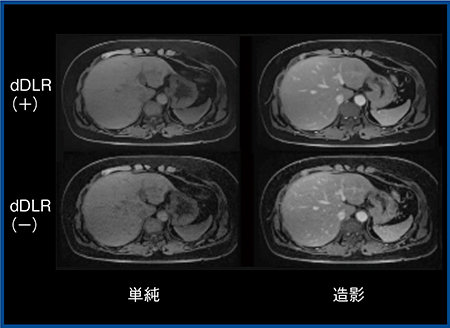

図4は腹部ダイナミックMRIで,従来法(b)では肝左葉外側区が胃と周囲の脂肪との部分容積効果によって辺縁を区別しづらいが,3D-CS+dDLR(a)では,同じ撮像時間の画像でも,空間分解能を向上できるため辺縁や肝の下面の境界も明瞭となっている。さらに,3D-CSの画像をdDLRの有無で比較すると,dDLRを適用した画像では画質が向上している(図5)。

図5 3D-CSにおけるdDLRの有無(W.I.P.)